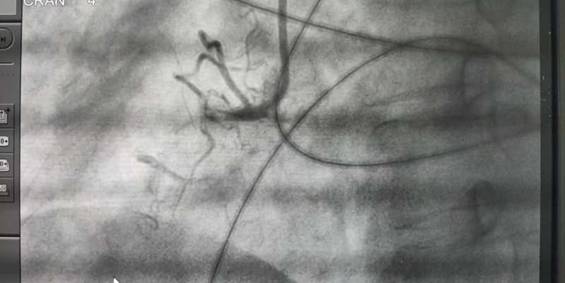

2019年1月23日,市中医院成功为4位患者进行了冠状动脉造影,同时为2名冠状动脉狭窄的患者进行了支架植入。支架植入和冠状动脉造影,是目前诊断、治疗心脏疾病最有效的手段,综合介入治疗中心先进的设备和精湛的技术,为人民群众看病就医带来极大方便,标志着市中医院心血管疾病诊治迈上新的台阶。

心脏介入治疗是一种新型诊断与治疗心血管疾病技术,无需开胸,在影像学方法的引导下,经过穿刺体表血管,借助某些器械,将导管送到病变部位,通过特定的心脏导管操作技术对心脏病进行确诊和治疗的诊治方法,它是目前较为先进的心脏病诊治方法,包括冠状动脉造影术、 PTCA +支架术、二尖瓣球囊扩张术、射频消融术、起搏器植入术、先天性心脏病介入治疗、冠状动脉腔内溶栓术等。